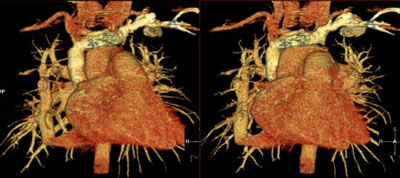

Patient has hypoplastic right lung and anomalous pulmonary venous return to the hepatic veins. Note the anomalous vein extending form the right hilum down to the diaphragm.